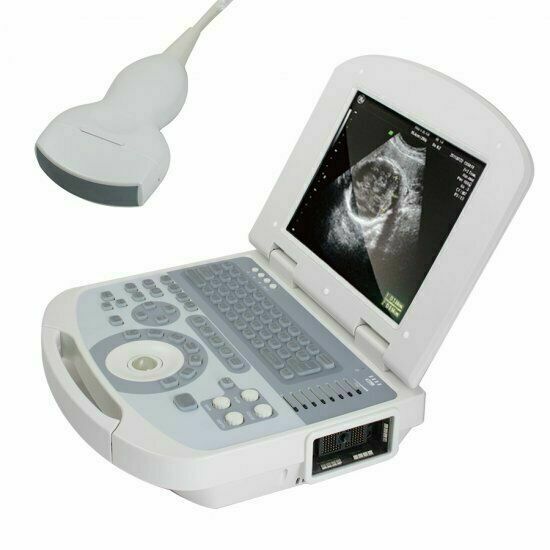

New Portable Laptop Machine Digital Ultrasound Scanner, 3.5 Micro Convex Probe

The new Portable Laptop Digital Ultrasound Scanner features a 3.5MHz micro convex probe for versatile imaging capabilities. This compact machine is designed for high-quality diagnostics in various medical settings, providing detailed ultrasound images. Its lightweight design and user-friendly interface make it ideal for healthcare professionals who require mobility and ease of use. The scanner is suitable for a range of applications, ensuring accurate assessments and improved patient care. Overall, it's a reliable solution for modern medical imaging needs.